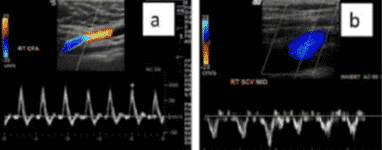

¿Cómo diferenciarlas?

En el caso de existir dudas, el método más fiable para diferenciarlas seria la realización de un Doppler pulsado donde las venas se representan como una onda bifásica y a veces una retrograda de baja velocidad; mientras que la arteria presenta un flujo fundamentalmente sistólico de alta velocidad.

La ventaja de contar con Doppler a color es que este modo aporta información sobre la existencia y movimiento del flujo sanguíneo, siendo posible localizar regiones con flujo anormal. Queda representado de la siguiente forma:

- Color rojo: flujo que se acerca al transductor.

- Color azul: flujo que se aleja del transductor.